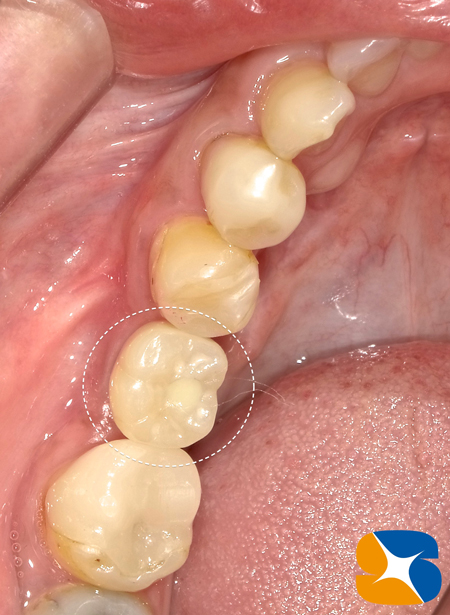

4ヶ月前に行った治療(ブログにも掲載)が、無事に完了しました。

当院では、1ヶ月間、必ず「噛み慣れ」のための仮歯を使用して頂いています。

慣らし噛みでも問題が無かったので、セラミックの白い歯にチェンジして最終完成となりました。

•はじめは噛むのが恐かったけど、直ぐに慣れた。

•仮の歯物でよく物が挟まったので、本物の歯を入れる時には歯の形を代えてもらって

自分の歯とインプラントの歯との間に物が詰まりにくくなった。

•たった1本の歯だけど、あるのと無いのとでは全然違う。ご飯が美味しいく頂けるのが幸せ。